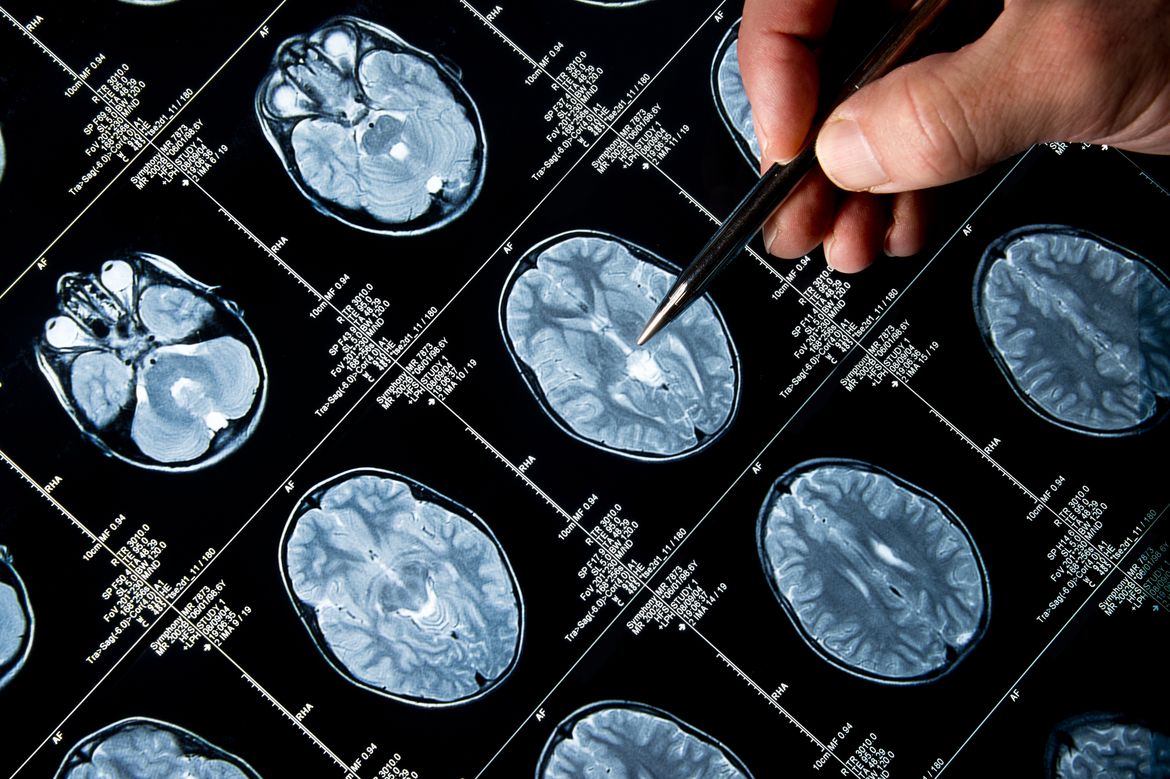

Benjamin Ellingson, director of the UCLA Brain Tumor Imaging Laboratory and a member of the Jonsson Cancer Center, was a key participant in the research that led to the clinical trial. He was involved in the radiographic evaluation of tumors in the study, which confirmed that there was a benefit of the targeted therapy. The study’s first author is Dr. Ingo Mellinghoff of Memorial Sloan-Kettering Cancer Center. The co-senior author is Dr. Patrick Wen of the Dana-Farber Cancer Institute.